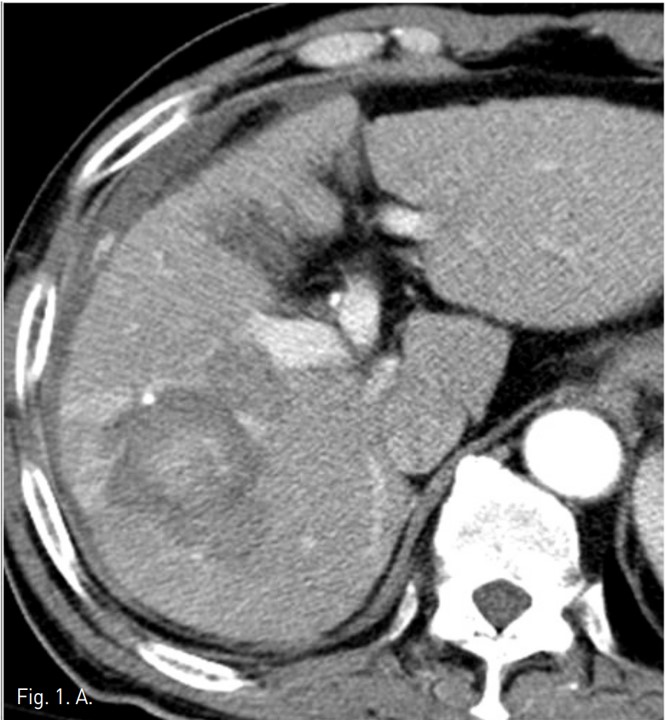

동맥기 간 CT 횡단면 영상에서 간우엽에 두 개의 간암의 크기가 증가되어 고주파 열치료를 시행하였다. 시술후 추적 CT에서 간우엽의 표면을 따라 조영제가 혈관 밖으로 흐르는 것이 발견되었고, 출혈성 복수의 양이 증가되었다 (Fig. 1).

Fig. 1. Dynamic liver CT arterial (A) and portal (B) phase scans show extravasation (arrows) of contrast materials at the surface of the liver and hemoperitoneum around the liver. The focus of extravasation was not clear.